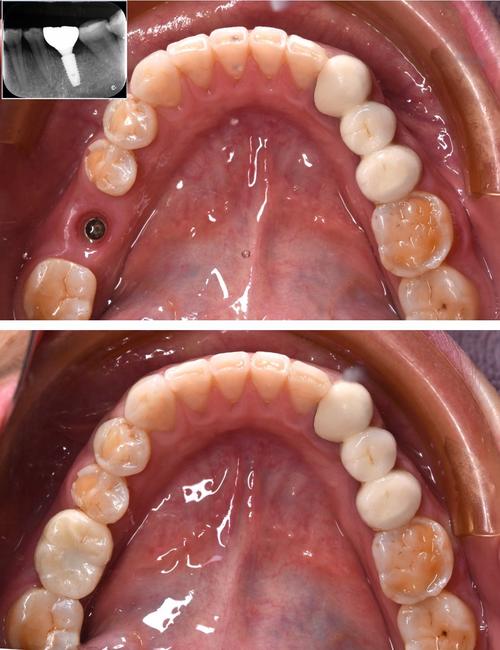

基台连接与取模:

- 骨结合完成后,医生会进行二期手术(有时是微创方式),暴露种植体顶部,连接基台(连接种植体和牙冠的中间部件)。

- 然后取模,制作最终的牙冠(通常为全瓷冠)。

戴牙冠:

(图片来源网络,侵删)- 牙冠制作完成后(通常需要1-2周),医生会将其固定在基台上。

- 调整咬合,确保舒适、功能正常、美观自然。